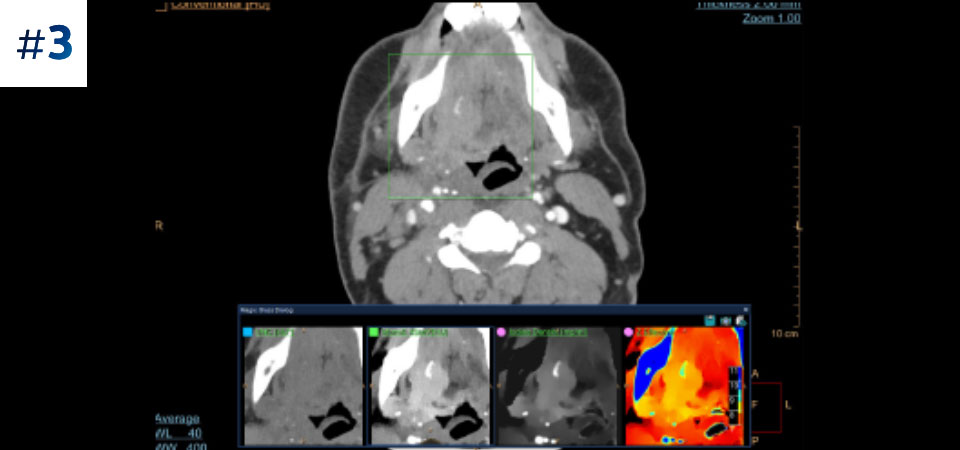

Prin tomografia computerizată bazată pe detector spectral, puteți achiziționa date la mai multe nivele de energie - convenționale și spectrale – printr-o singură expunere și fără protocoale speciale de scanare, pentru o mai bună caracterizare și vizualizare a țesuturilor.

Scanează ca de obicei O singură scanare pentru date convenţionale şi spectrale obţinute rapid, cu doză redusă, pentru fiecare pacient, de fiecare dată.

Are întotdeauna disponibilă componenta spectrală Rezultate 100% spectrale, pentru toate scanările care sunt întotdeauna disponibile la cerere, chiar și retrospectiv.

Reduce numărul de examinări ulterioare O mai bună caracterizare și vizualizare a țesuturilor poate reduce nevoia de scanare ulterioară pentru examene suboptime și descoperiri accidentale.

Se adresează tuturor tipurilor de pacienți Sistemul poate fi utilizat pentru diverse tipuri de pacienţi, de la copii şi adolescenţi până la pacienţi bariatrici.